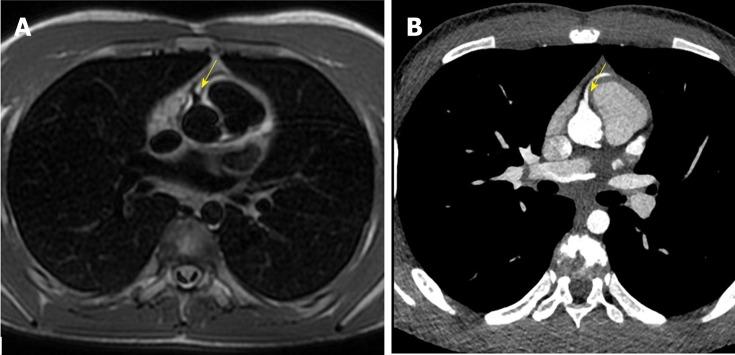

A healthy 10-year-old male patient was referred to the Radiological Department of our Institution due to no evidence of left coronary artery in echocardiographic examination. With C-MRI was detected marked myocardial trabeculation and was suspected anomalous origin and course of left circumflex (LCx) artery and of left anterior descending (LAD) artery. With third generation Dual Source C-CT 192x2-sections (SOMATOM Force, Siemens, Germany) was confirmed anomalous origin of LCx artery from right pulmonary artery associated with anomalous origin of LAD artery from right coronary artery with course in front of right ventricular outflow tract. The patient underwent surgical treatment with reimplantation of the anomalous LCX and LAD arteries into the wall of ascending aorta, with no postoperative complications. The patient remained asymptomatic and follow-up C-MRI scan four months after operation showed complete success of surgery treatment.

一名10岁健康男性患者因超声心动图检查未发现左冠状动脉而被转诊至我院放射科。通过C - MRI检测到明显的心肌小梁,并怀疑左旋支(LCx)动脉和左前降支(LAD)动脉起源及走行异常。使用第三代双源C - CT 192x2层扫描(德国西门子SOMATOM Force)证实LCx动脉起源于右肺动脉,同时LAD动脉起源于右冠状动脉且走行于右心室流出道前方。该患者接受了手术治疗,将异常的LCX和LAD动脉重新植入升主动脉壁,术后无并发症。患者仍无症状,术后四个月的随访C - MRI扫描显示手术治疗完全成功。